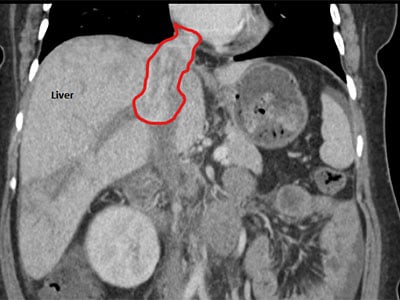

Morel’s surgery spanned two days. The tumor was situated in the inferior vena cava at the level of the hepatic veins, which drain de-oxygenated blood from the liver into the inferior vena cava. There was also cancer in the vena cava extending from the heart down toward the middle of the abdomen. The inferior vena cava is the large vein that returns blood to the heart from the body.

Surgeons had to transect multiple veins to get through to the tumor and had to be extremely cautious when removing it; if pieces broke off and lodged in the blood vessels leaving the heart to the lungs, it could kill Morel. They also removed her right kidney and 70% of her liver, which was even more difficult because chemotherapy damages the liver and causes excess bleeding. Ideally, surgeons don’t like to remove more than 60% of a cancer patient’s liver, but in Morel’s case they had to push the limit because they had no other choice.